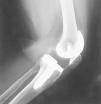

Se trata de una paciente de 69 años que fue diagnosticada de artrosis en la rodilla izquierda. En abril de 1994 se colocó una PTR Génesis I® (Smith and Nephew, Richards) preservando el ligamento cruzado posterior (LCP). Únicamente se cementó el platillo tibial, no protetizándose la rótula. Durante la cirugía el deslizamiento patelofemoral fue normal en todo el rango de movimiento. Trascurridas 48 horas tras la intervención, comenzó con un programa rehabilitador con artromotor. El arco de movilidad en los primeros tres meses era de 0-100°, la rodilla era indolora y estable, con un correcto alineamiento de los componentes. Al año de la intervención caminaba alrededor de dos horas sin bastones, pero precisaba de analgesia ocasional debido a un dolor patelofemoral con irradiación al hueco poplíteo y claudicación tras la sedestación («signo de la butaca»). El rango de movilidad empeoró a 0-80°. Estudios radiográficos con la proyección de Merchant mostraron una rótula centrada con un pequeño pinzamiento lateral y una ligera inclinación. Se indicó una protetización de la rótula y una operación de Ficat, pero fue desestimado por la enferma. Dos años y medio después la paciente caminaba sin bastones durante más de una hora por superficie llana, no podía bajar escalones ni siquiera de forma recíproca y se quejaba de rigidez de la rodilla al iniciar la deambulación. El dolor empeoró y la movilidad fue de 0-55°. Los estudios para detectar infección fueron negativos. Las radiografías seriadas mostraron una progresiva retracción del tendón rotuliano, llegando hasta el 25% y una rótula cada vez más descendida. Antes de la cirugía, la puntuación de la Sociedad Americana de Rodilla (KSS) era de 29 + 30, el polo distal de la rótula contactaba con el labio anterior del polietileno (fig. 1) y el arco de movilidad era 0-25°. El índice de Insall-Salvati era de 0,73, Blackburne de 0,69 y Caton de 0,69.

Figura 1. Retracción del tendón rotuliano y rótula baja.